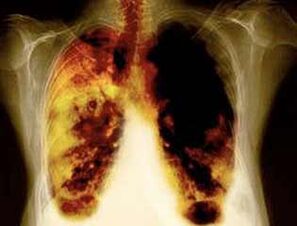

- Zmanjšanje tveganja za razvoj pljučnega raka in številne druge vrste raka.

- Zmanjšanje tveganja za razvoj nekaterih pljučnih bolezni (na primer kronična obstruktivna pljučna bolezen).

- 10 let po prenehanju kajenja za 40%se verjetnost pljučnega raka zmanjša za 40%.